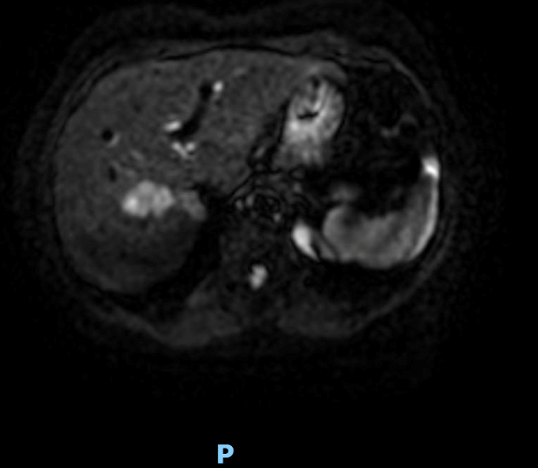

Panoramic imaging was subsequently performed: a CT scan followed by MRI confirmed the suspicion of malignancy, without evidence of biliary dilatation or vascular invasion (Figs. 3 and 4); however, a definitive diagnosis could not be established.